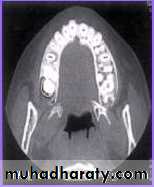

CT Scan

By Ericson & Kurol Used to diagnose the exact

position of an impacted tooth.

Clear serial radiographs may be

taken at graduated depth in any

part of human body in this

method.

This technique allows the

elimination of superimposition

of other structures.

It is however rarely used in the

diagnosis of impacted teeth

because of

(1) Large radiation dosage.

74

CBCT

Cone beam

computedtomography

(or CBCT, also

referred to as C-arm

CT, cone beam

volume CT, or flat

panel CT) is a

medical imaging

technique consisting

of X-ray computed

tomography where

the X-rays are

conventional radiography does

information.76

CBCT is more accurate than

conventional techniques inlocalising impacted maxillary

canines.

CBCT is more reliable than

conventional techniques There is no robust evidence

that supports using CBCT as

the first line imaging technique.

We should only use it when

Cone-beam computed tomography vs conventional radiography in visualization

of maxillary impacted-canine localization: A systematic review of comparativestudies. Ehsan Eslami et al. Am J Orthod Dentofacial Orthop 2017;151:248-58